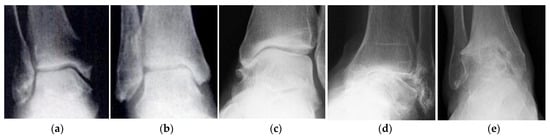

- Ankle X-ray: Indications, Conduct, Results. Available online: https://ocrb.ru/lechenie/rentgenografiya-golenostopnogo-sustava.html (accessed on 15 December 2020).